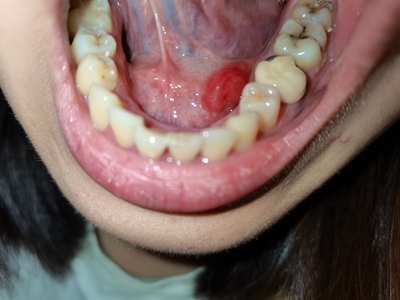

舌下腺囊肿舌头底下的筋旁边长个球形疙瘩图

舌下腺囊肿位于舌系带一侧的口底黏膜下,表现为表面光滑的球状大疙瘩,常继发感染导致局部肿胀、疼痛,呈进行性增大,并越过舌系带在对侧隆起。